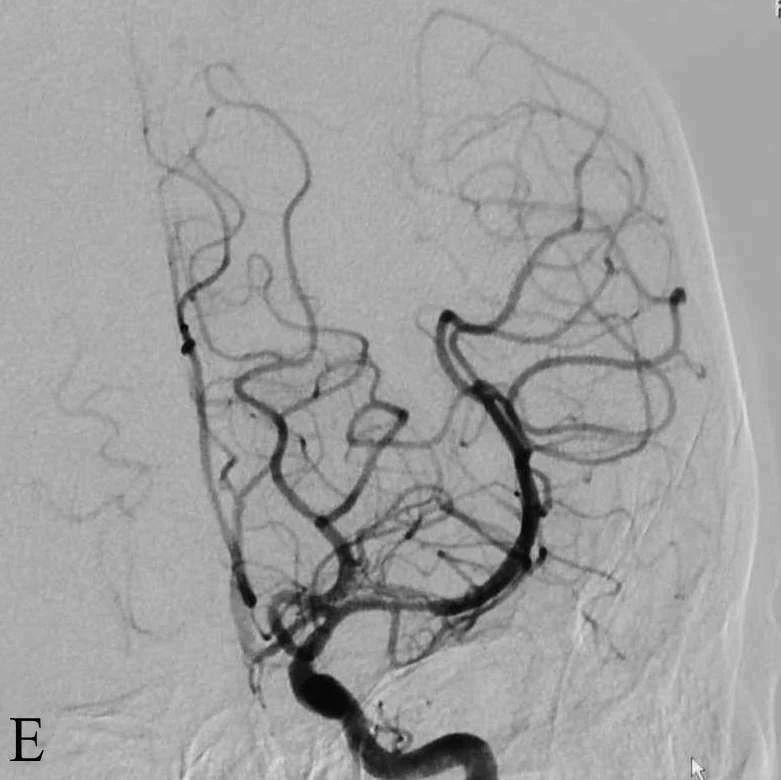

E:取栓后左侧ICA造影正位显示左侧ICAmTICI3级再通